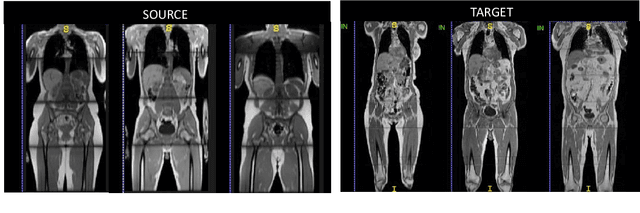

Abstract:The variations in multi-center data in medical imaging studies have brought the necessity of domain adaptation. Despite the advancement of machine learning in automatic segmentation, performance often degrades when algorithms are applied on new data acquired from different scanners or sequences than the training data. Manual annotation is costly and time consuming if it has to be carried out for every new target domain. In this work, we investigate automatic selection of suitable subjects to be annotated for supervised domain adaptation using the concept of reverse classification accuracy (RCA). RCA predicts the performance of a trained model on data from the new domain and different strategies of selecting subjects to be included in the adaptation via transfer learning are evaluated. We perform experiments on a two-center MR database for the task of organ segmentation. We show that subject selection via RCA can reduce the burden of annotation of new data for the target domain.